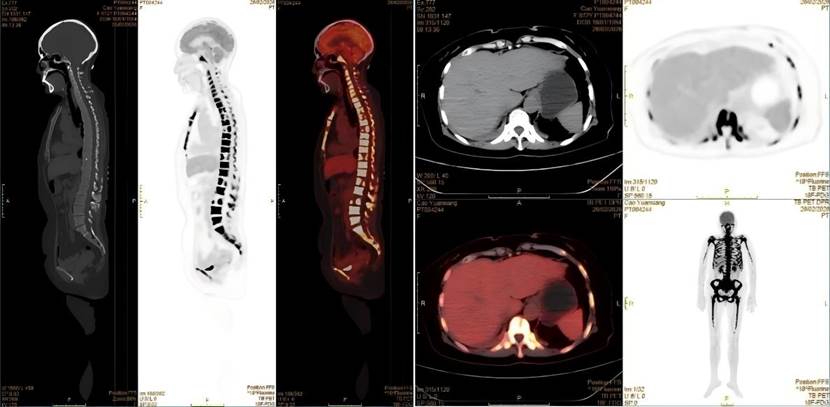

经PET-CT检查,患者全身骨弥漫性明显代谢增高,其他脏器均并未找到明确的实体原发灶,这样的显像结果推翻了肿瘤骨转移的初步诊断。核医学科医生看到这样的显像结果,并结合患者的临床表现,一个新的诊断方向在脑海中回荡:淋巴瘤?血液系统疾病?按照这一方向,为患者进一步进行了骨髓穿刺等检查,终于这个凶手被找到——急性淋巴细胞白血病

△患者PET-CT的显像图

急性淋巴细胞白血病是一种起源于淋巴细胞的恶性肿瘤,其异常增生的白血病细胞会浸润全身骨骼和骨髓,破坏骨代谢平衡,导致骨骼出现弥漫性代谢活跃和浓聚表现。这正是患者在PET-CT和骨扫描上出现异常浓聚的原因。同时,患者持续发热、体重骤降等症状,也是白血病细胞大量增殖、释放致热原并抑制机体正常免疫功能的典型表现。